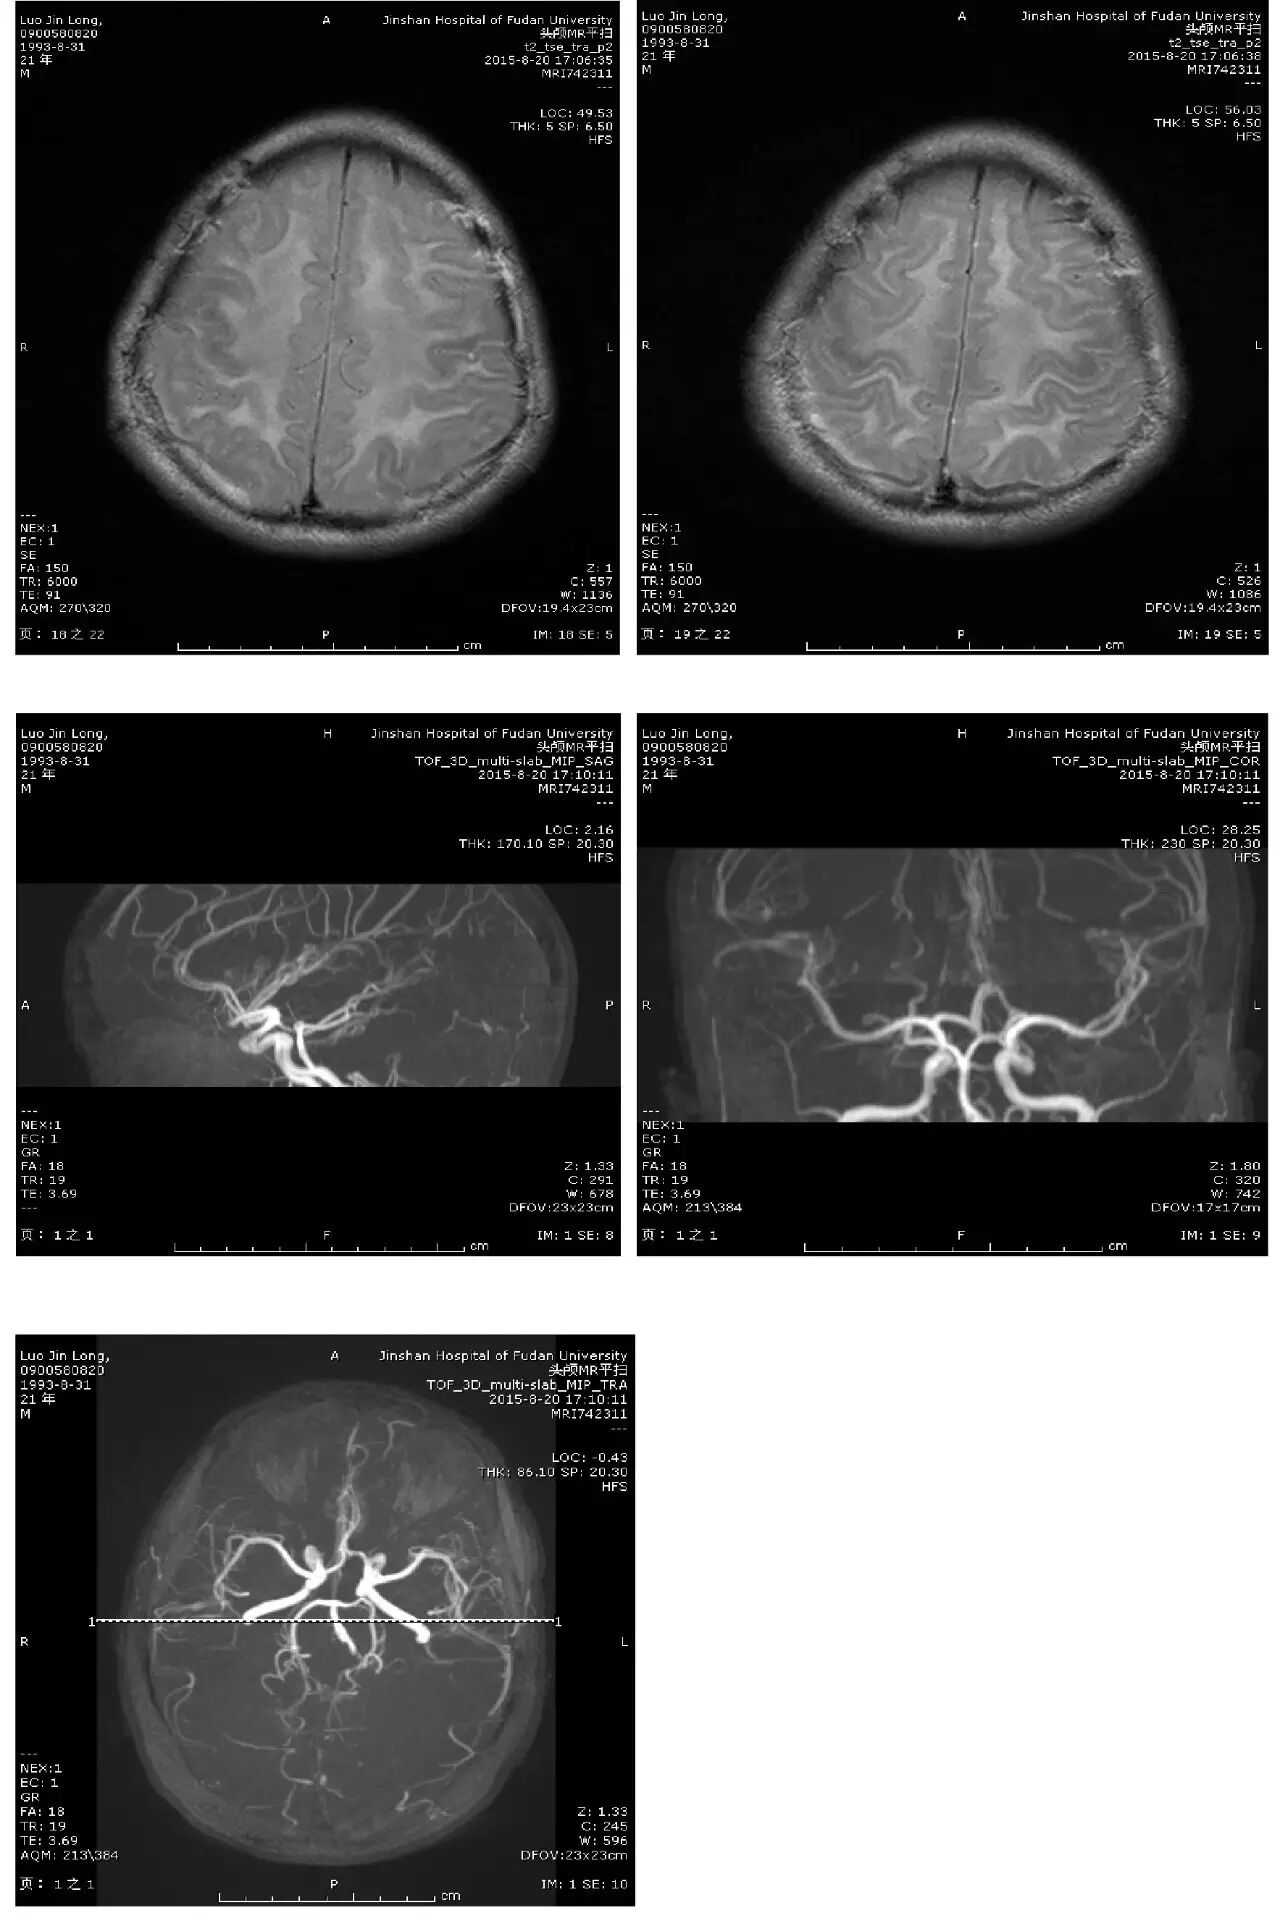

主诉:头痛、反应迟钝、口齿不清4天

现病史:头中线部位钝痛,反应迟钝,口齿不清,无发热,无恶心、呕吐,无饮水呛咳,四肢乏力。无麻木不适。2天后出现视物模糊。外院头颅CT:两侧大脑半球低密度灶。